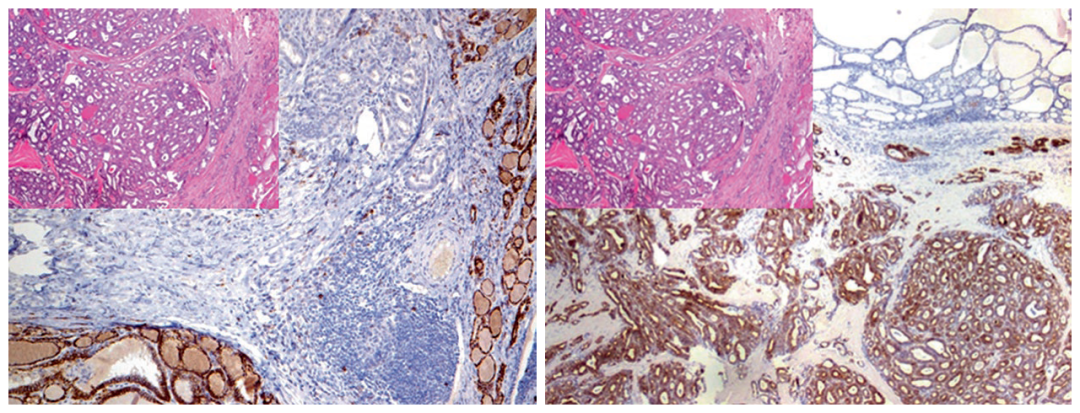

图1. (左)正常甲状腺组织CD56阳性,而甲状腺乳头状癌则并不表达。(右)甲状腺乳头状癌CK19阳性,而正常甲状腺组织并不表达。